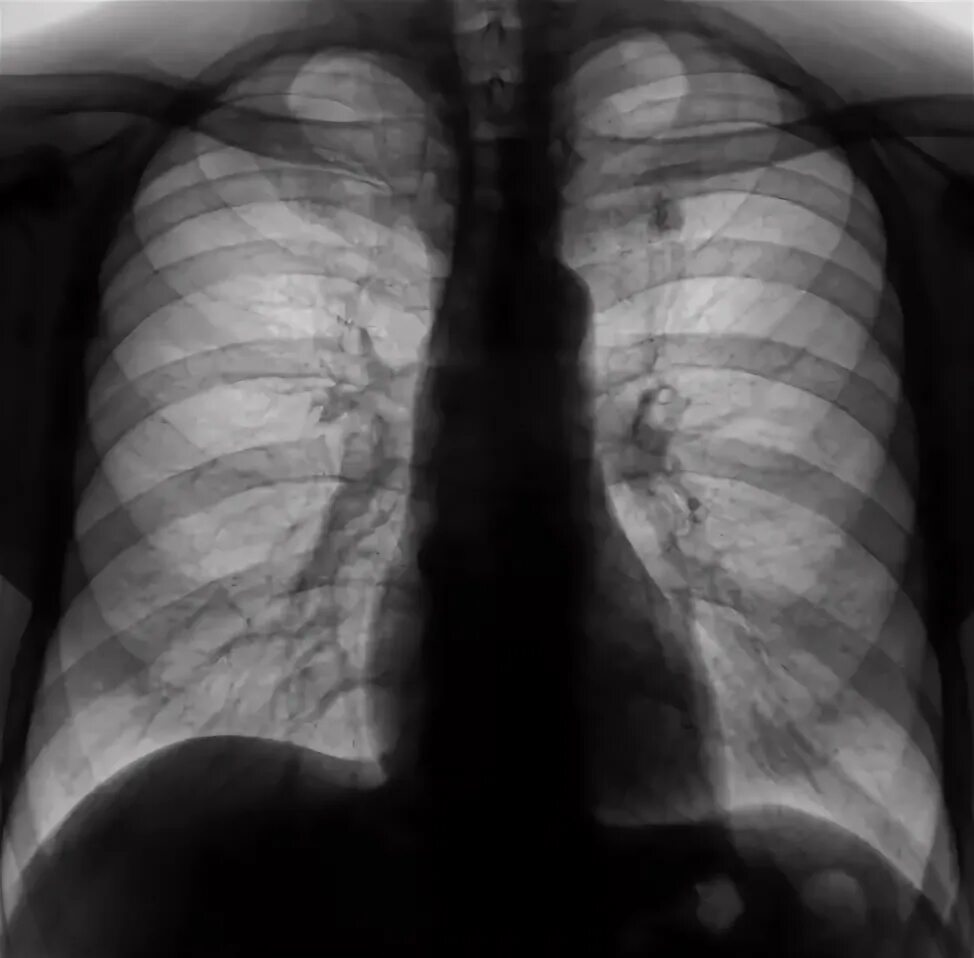

S9 сегмент левого легкого. снимок легких. s9 s10 левого легкого. левое легкое s9 s10 пневмония.

Пневмония слева s7-s8. пневмония s10 левого легкого на кт.

Пневмония s2-s6. пневмония s9 справа.